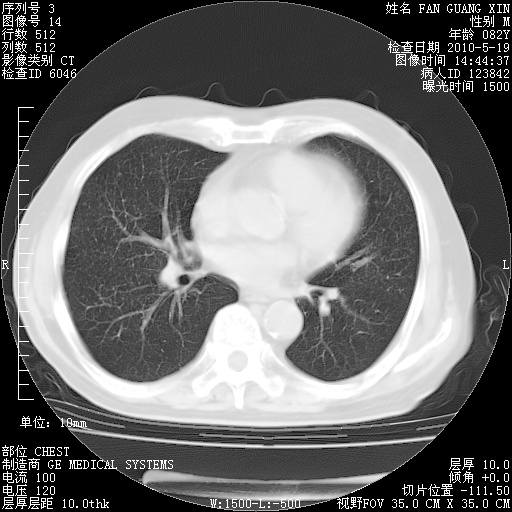

可改为口服强的松40-50mg/d治疗,若病情仍稳定,胸部阴影不再吸收可逐渐减量